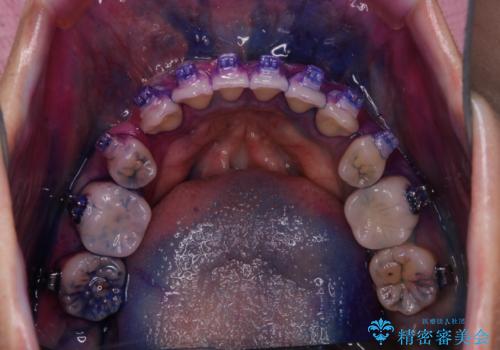

ワイヤー矯正中に歯の染め出し

- ワイヤー矯正中にクリーニンング希望とのことでした。染め出しを行い歯磨き指導とPMTC60分コースを行いました。